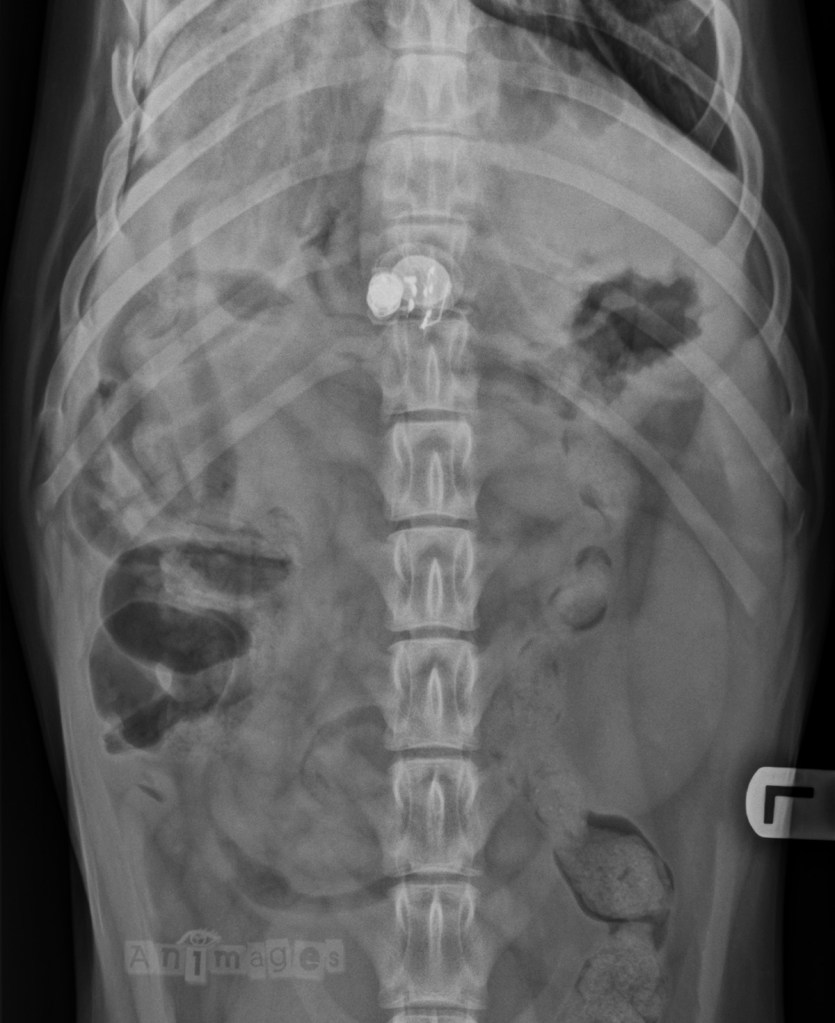

Ventrodorsale